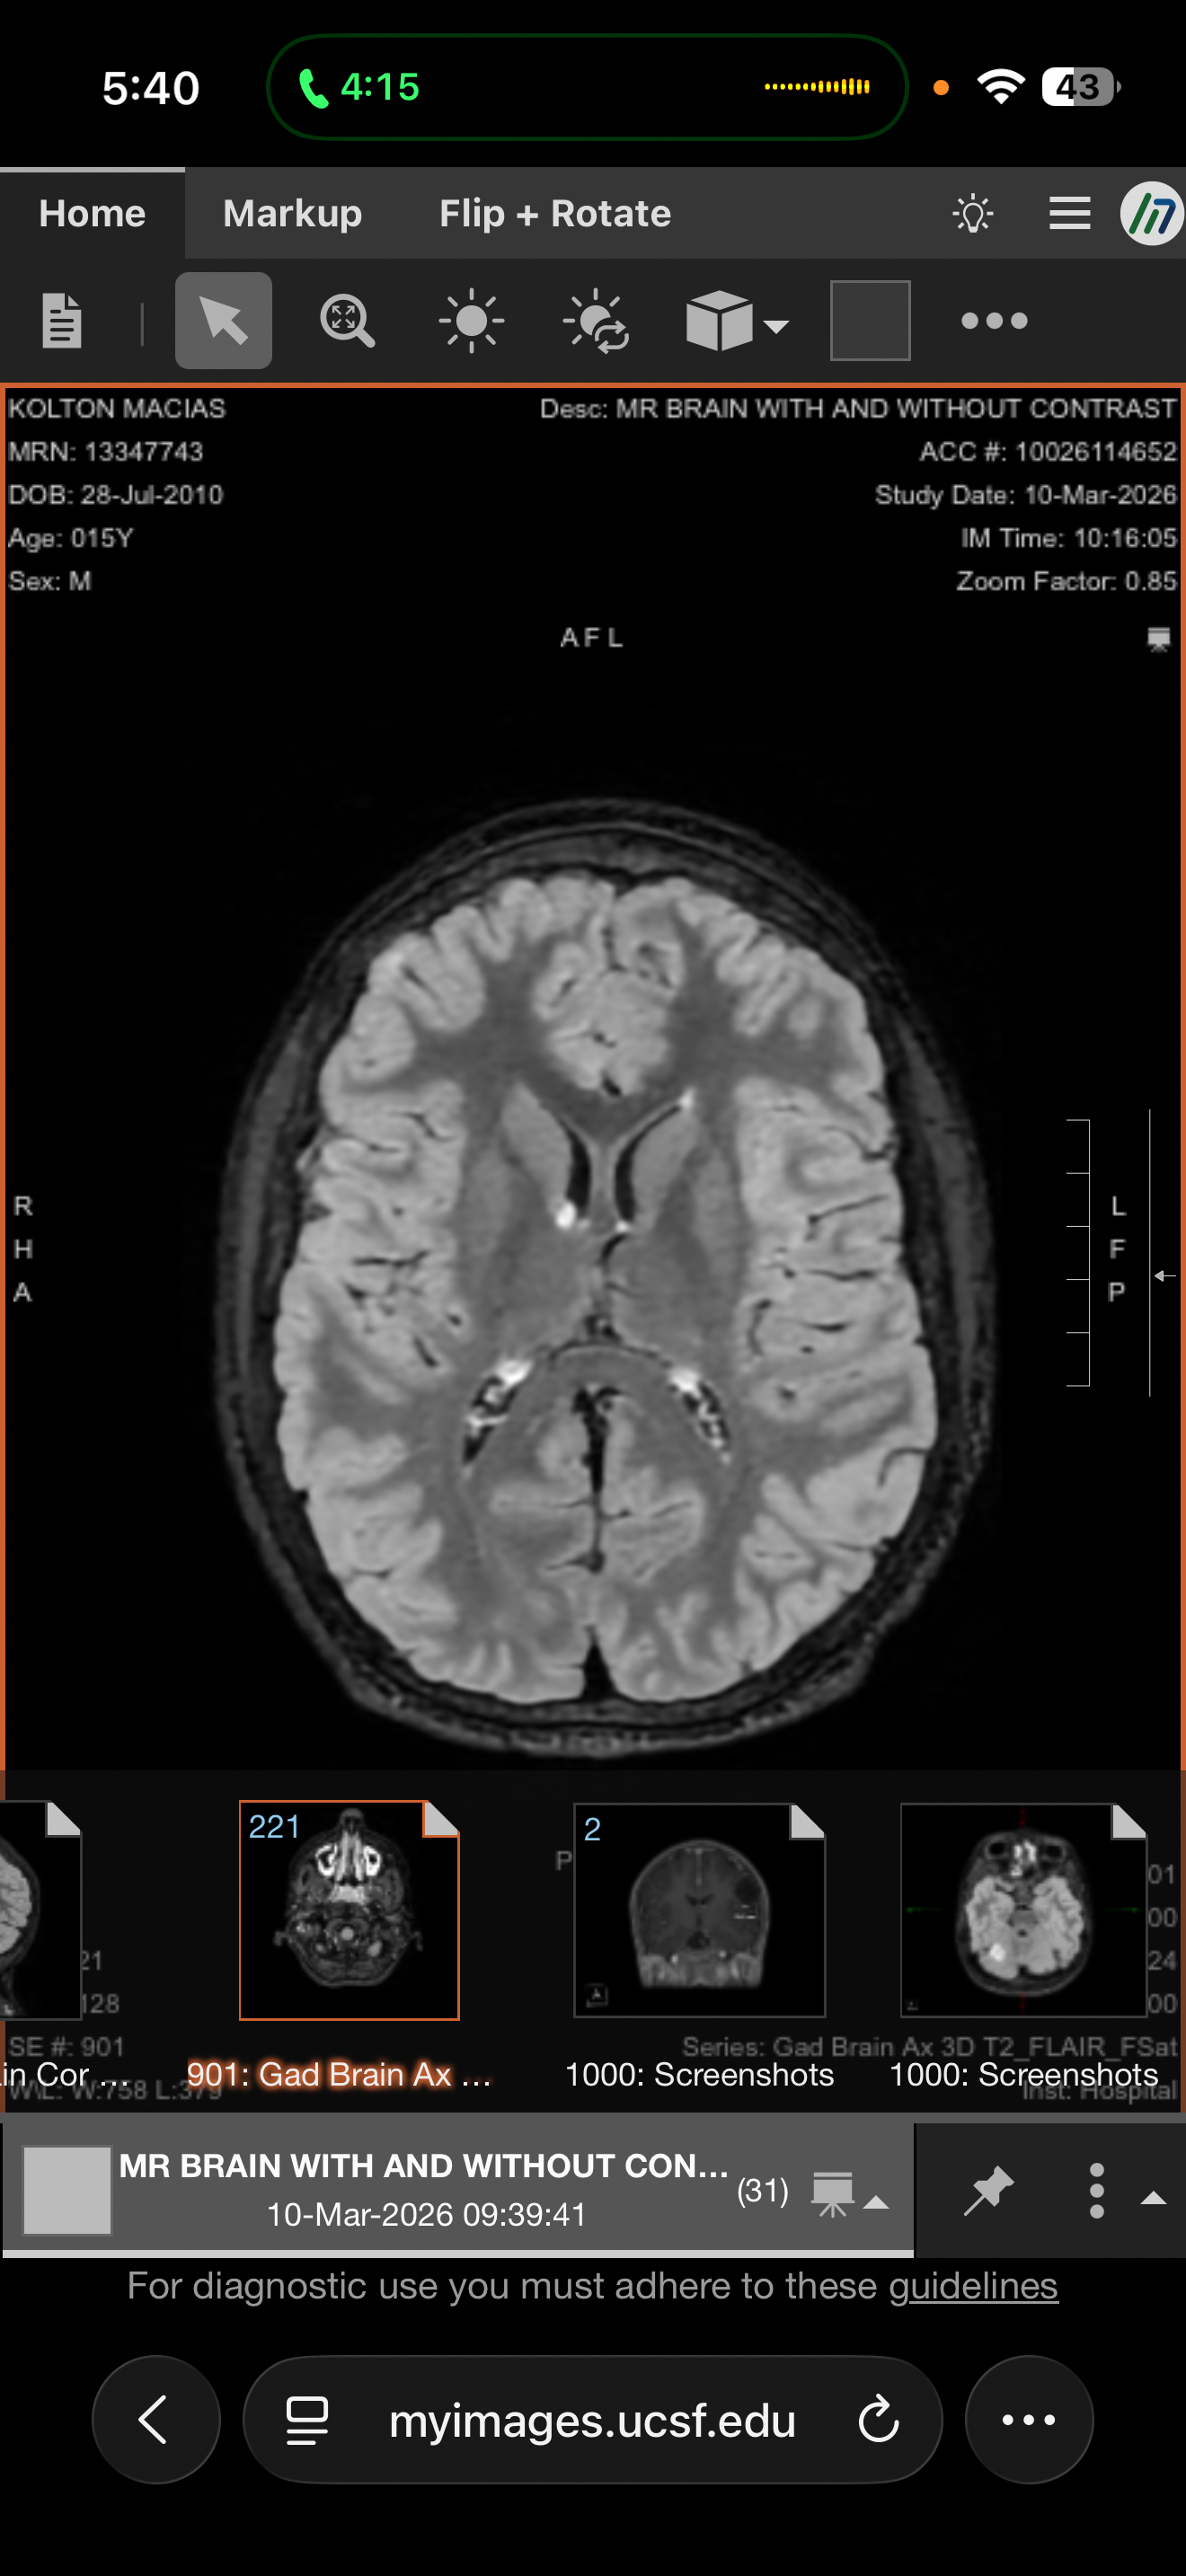

Our hearts are heavy as we share that Kolton has recently been diagnosed with multiple brain tumors. After urgent evaluations, doctors discovered four tumors, including one located in the cerebellum. At this time, Kolton’s medical team is moving forward with a biopsy and laser ablation procedure to treat one of the tumors. The remaining tumors are expected to be managed with oral medications and ongoing treatment. This journey will require frequent monitoring, including MRIs every 3 months, and close follow-up with specialists.